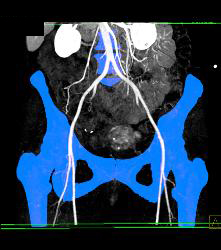

Sgap Flap Planning to Define Gluteal Arteries